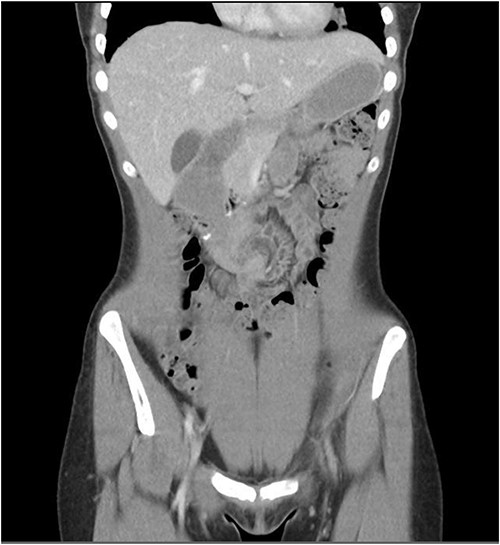

A 23 year old female underwent a laparoscopic duodenojejunostomy for SMA syndrome. The duodenum was accessed infra-colic and the second part of the duodenum was anastomosed to the proximal jejunum 60 cm from the duodenojejunal (DJ) flexure (Fig. 1).

She presented to the surgeon’s rooms with a history of 9 days of postprandial vomiting 9 months later. A computed tomography (CT) showed a volvulus immediately adjacent to the duodenojejunostomy anastomosis causing a small bowel obstruction (Fig. 2).